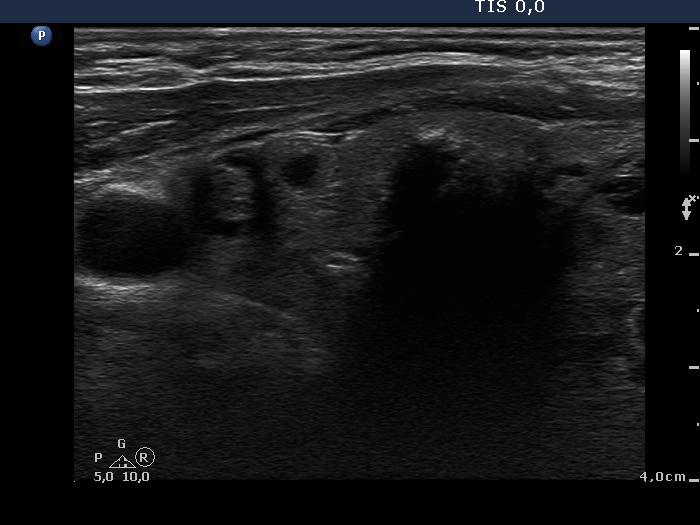

Benign nodular hyperplasia - Case 49. (ultrasonographic picture 2)

Right lobe, longitudinal scan. There are multiple discrete lesions without oncological significance.